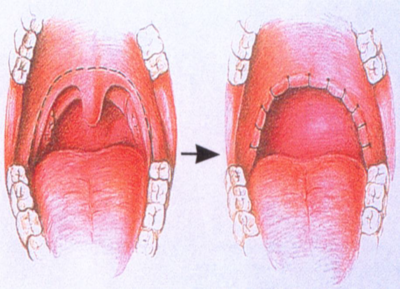

人は通常上気道を広げる筋肉が緊張していて、気道を広げて、呼吸している。眠りが深くなるとこの緊張が解けて、気道が狭くなるとともに、舌の根元がのど側に下がって食道と気道とを切り替えている軟口蓋を塞ぎ、気道が狭くなり、いびきが生じ、これがはなはだしい場合、気道が閉じて無呼吸となる。

- 小児で扁桃腺・アデノイドが大きくて発症している場合は、扁桃・アデノイドの治療をする。